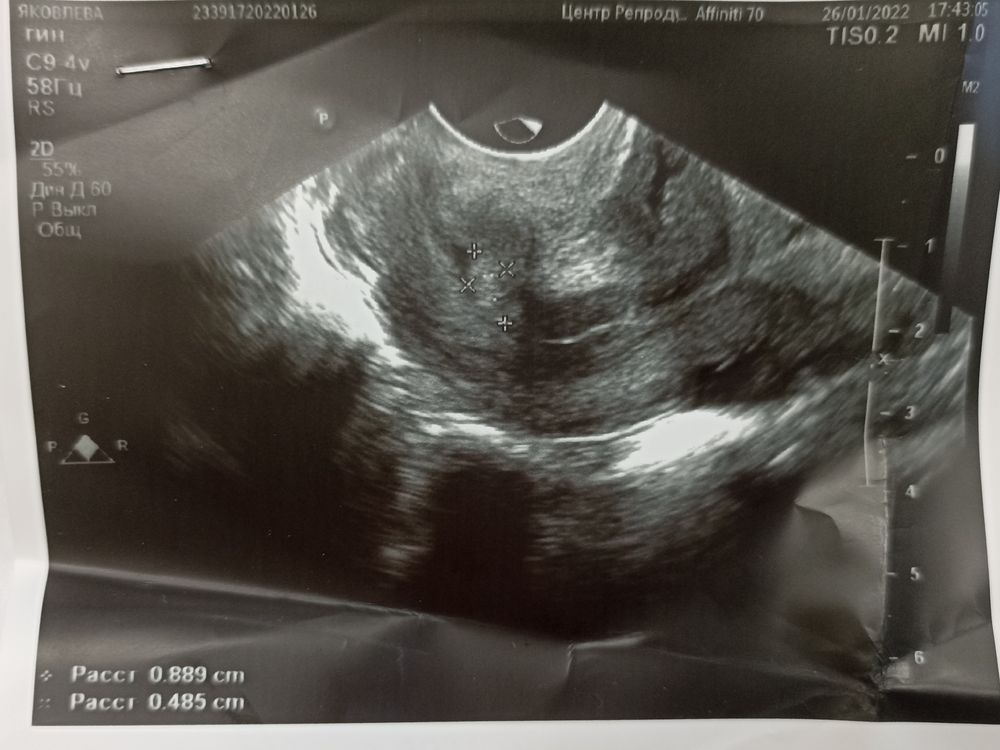

Последний раз на УЗИ была 26.01. Вот что мне написали... Я очень сильно переживаю... Я не нахожу себе места.... Я не понимаю что происходит, хгч которое пришло 18 числе тоже вроде как не соответствовал 4 акушерским на тот момент... А был он в норме для ДВУХ НЕДЕЛЬ

Yulia, у меня вопрос возник про то что пя 3мм для акушерских 6 недель ничтожно мало, меня напугали что это замершая или внематочная..... Яйцо что как будто корявое, они в УЗИ даже не написали что это пя, а просто анэхогеннное включение, я прекрасно понимаю что от 1000 видео, судя по неделям акушерским у меня хгч должен быть уже более 1000,поэтому и поникую. А на УЗИ ездила по тому что так надо было

Катерина, простите, вы внимательно прочитали???? У меня хгч когда было 4 недели был как на второй неделе и плодное яйцо корявое сказалт соответствует где то неделям 4 с натяжкой... И то они даже не написали что это пя и оно всего 3 мм, для 6 недель это очень очень мало

У меня сейчас 6 акушерских не день уже, а пя 3мм, оно не соответствует неделям, так же как и хгч..... 18 числа у меня по сроку 4 недели, а хгч показал только 2